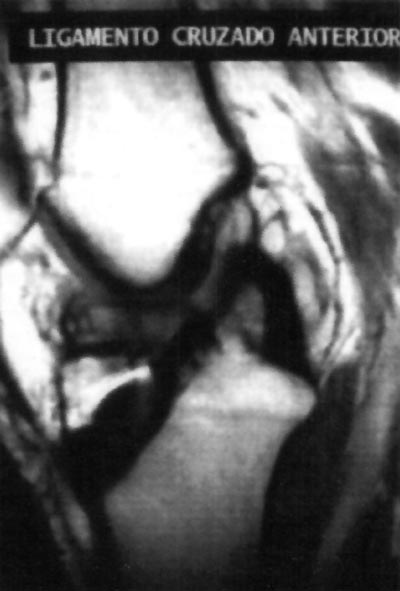

En el examen físico se constató limitación de 5° en la extensión de la rodilla acompañada con dolor sin referir un traumatismo evidente. Las radiografías no mostraron alteración osea y ubicación correcta de los tornillos interferenciales (Fig.1). La RM evidenció la presencia de un nódulo de 1,3 cm de espesor de baja señal compatible con tejido fibroso nivel del túnel intercondíleo inmediatamente anterior al injerto (Fig.2). Ante los hallazgos del examen físico y los estudios complementarios, se le realizó una artroscopia en diciembre del 2002.

10_02_08_fig2

Figura. 2: Imagen de RM que muestra un nodulo de baja señal de intensidad compatible con tejido cicatrizal ubicado anteriormente al neoligamento en el surco intercondíleo.